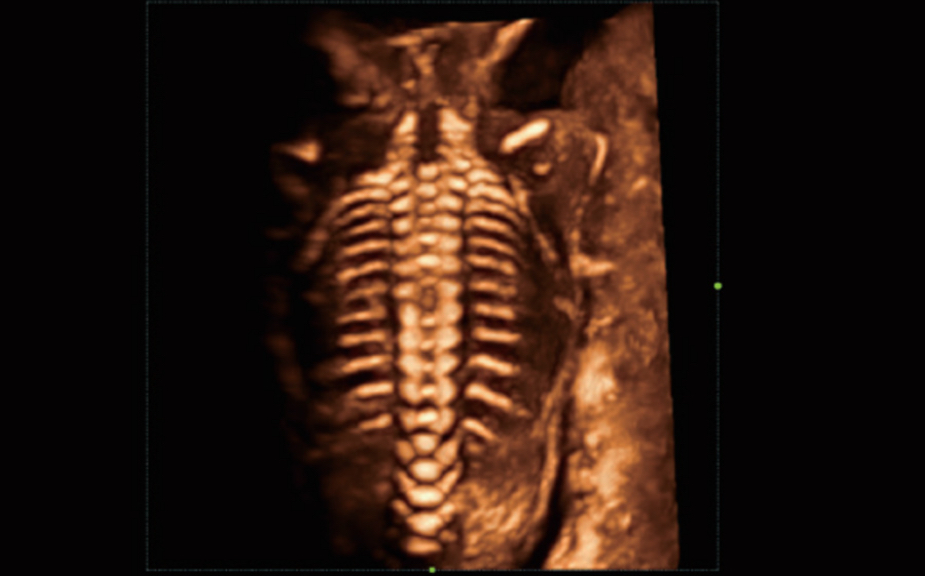

Nuewa I9? ??? ???? ?? ??? ?? ??? ???? ?? ??? ???? ???? ??? ?????. ??? ??? ??? ?? ????? ?? ???? ???? ???? ???? ??? ???? ??? ??? ???? ??? ???? ??? ?? ?????.

ZST+ ???? ???? ??? ???? ??? ?????. ??? ????? ??? ? ???? ?? ??? ?? ????? ?????. ?? ???, ?? ???, ?? ??? ?? ?? ?? ??? ??? ???? ???? ??? ?? ??? ?? ???? ?? ??? ?? ??? ?????.